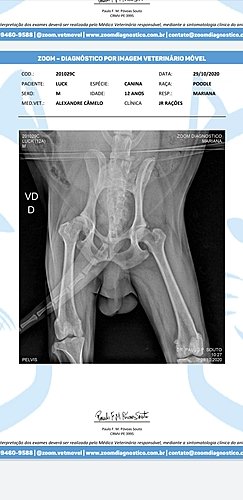

Luck é meu cachorro a 12 anos, até dia 27/10 ele tava andando normal, fomos passear de manhã, mas de tarde ele perdeu a força nas patinhas traseiras, levei ele no veterinário Alexandre dia 28/10 e ele passou 2 medicamentos prediderme 20mg (38,80)e cronidor 12mg 2x ao dia por 20 dias que dá 2 caixas com 10 comprimidos (2x 59.90) e um raio x (200,00), todos esses já comprei e ainda preciso pagar + consulta (70,00). Fora isso, depois que saiu o resultado do raio x alexandre passou o tratamento pra 2 meses com o remédio Gerioox 2 Comprimidos por dia, que dá 4 caixas de 30 comprimidos pra os 2 meses, as 4 caixas são (425,12) + 75,00 (Seniox) + 71,90 (Milgama- esse será pra o resto da vida). A conta total disso fica em 1.001, 00. Dinheiro que foge muito do meu orçamento, me encontro totalmente seNm saber o que fazer e pedindo a vocês qualquer contribuição. É muito doloroso ver ele da forma que está pois ele sente muita dor, não anda devido a isso e tem dificuldade pra defecar porque é uma região proxima que ao fazer força pra defecar doi as articulacoes também e tudo isso tem como melhorar se eu conseguir seguir o tratamento. Preciso muito da ajuda de vocês, eu nem sei como agradecer, quem não puder doar, compartilha, vai ajudar muito. Eu quero muito que meu bichinho fique bem, o Veterinário disse que ele pode voltar a andar e não sentir dor. Muita gratidão a quem ajudar seja de que forma for. Muita gratidão, mesmo.

*** Vou anexar fotos do diagnóstico, dos preços de remédios e etc.